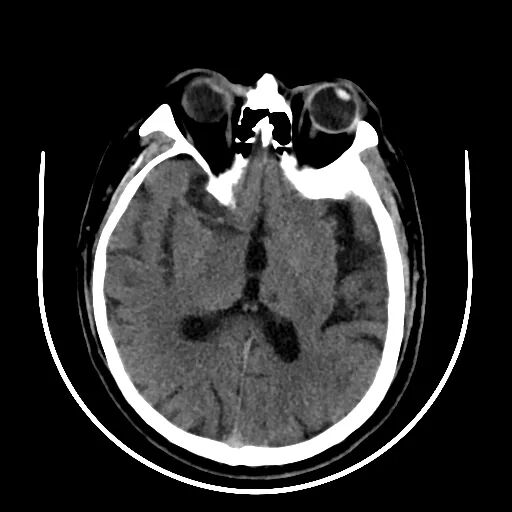

术后24小时查体:不完全运动性失语,双眼位正常,眼球活动自如,右侧中枢性面舌瘫,右侧上肢肌力3级、下肢肌力4级,右侧病理征(+),NIHSS=5,给予阿司匹林+氯吡格雷双抗。

术后颅脑CT无出血: